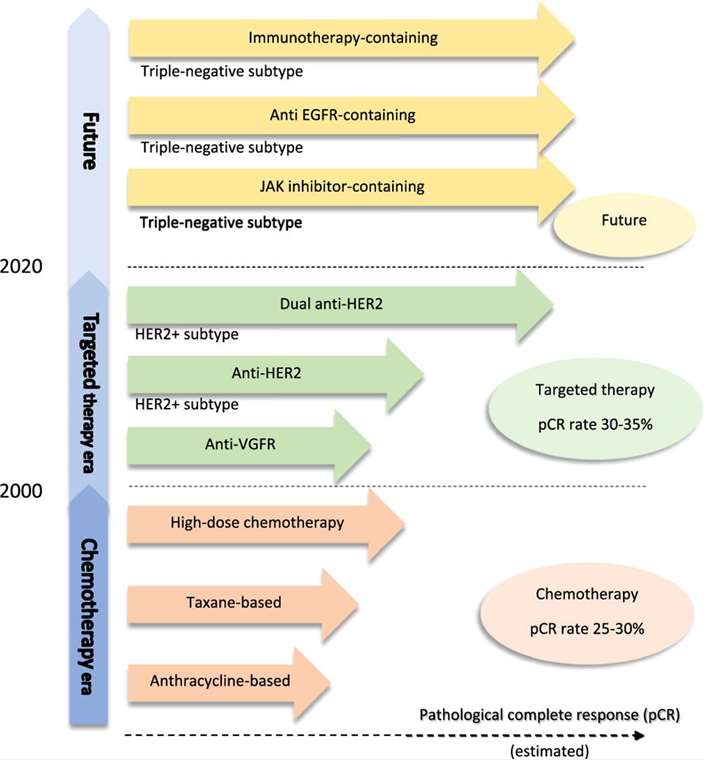

Fig.1 Update on systemic treatment for inflammatory breast cancer. (Chainitikun S., et al. 2020)

Fig.1 Update on systemic treatment for inflammatory breast cancer. (Chainitikun S., et al. 2020)